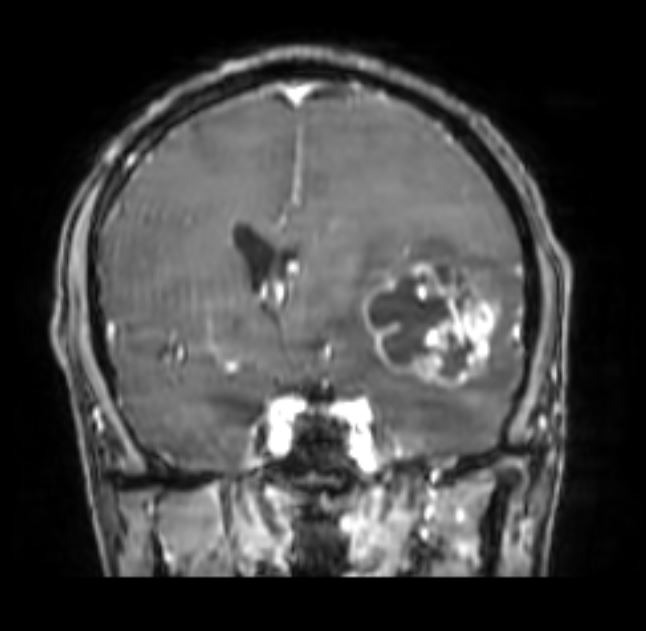

Ασθενής 52 ετών με εξεργασία εγκεφάλου ύποπτη για γλοιοβλάστωμα και διαταραχές ομιλίας μικτού τύπου.

Αποφασίστηκε η διενέργεια κρανιοτομίας για αφαίρεση του όγκου. Λόγω της εγγύτητας της βλάβης με κρίσιμες (eloquent) περιοχές του εγκεφάλου όπως είναι τα κέντρα και δεμάτια του λόγου, η νήσος του Reil και η πυραμιδική οδός (οδός της κίνησης άνω και κάτω άκρων) το χειρουργείο έγινε με τον ασθενή ξύπνιο (awake craniotomy) και με τη χρήση διεγχειρητικού υπερήχου, ανοσοφθορισμού 5-ALA και διεγχειρητικού νευροφυσιολογικού ελέγχου (neuromonitoring).

Η μετεγχειρητική μαγνητική τομογραφία ανέδειξε πλήρη εξαίρεση του όγκου.